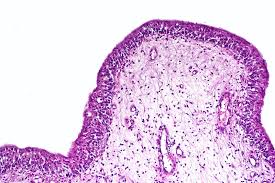

How long does urethritis last. Urethritis how long do symptoms last? Asymptomatic urethritis can last for a long time, always see a doctor if you are suspect a urinary tract infection and be tested and treated. How long does novel coronavirus last in a person? How long does teething last? The vast majority of urethritis cases require antibiotic treatment. How long does urethritis take to heal? (feel free to click on the links read on as i tell you exactly how long a regular uti, a complicated uti, and chronic utis should last.

1 depending on the strength and type of antibiotic, the doctor will prescribe an course of antibiotics that will last anywhere from 3 to 10 days. Asymptomatic urethritis can last for a long time, always see a doctor if you are suspect a urinary tract infection and be tested and treated. Discover in just 7 short questions why you may. You should continue your course of antibiotics according to the prescribing doctors instructions. If you don't want to share, here's what the stats say.